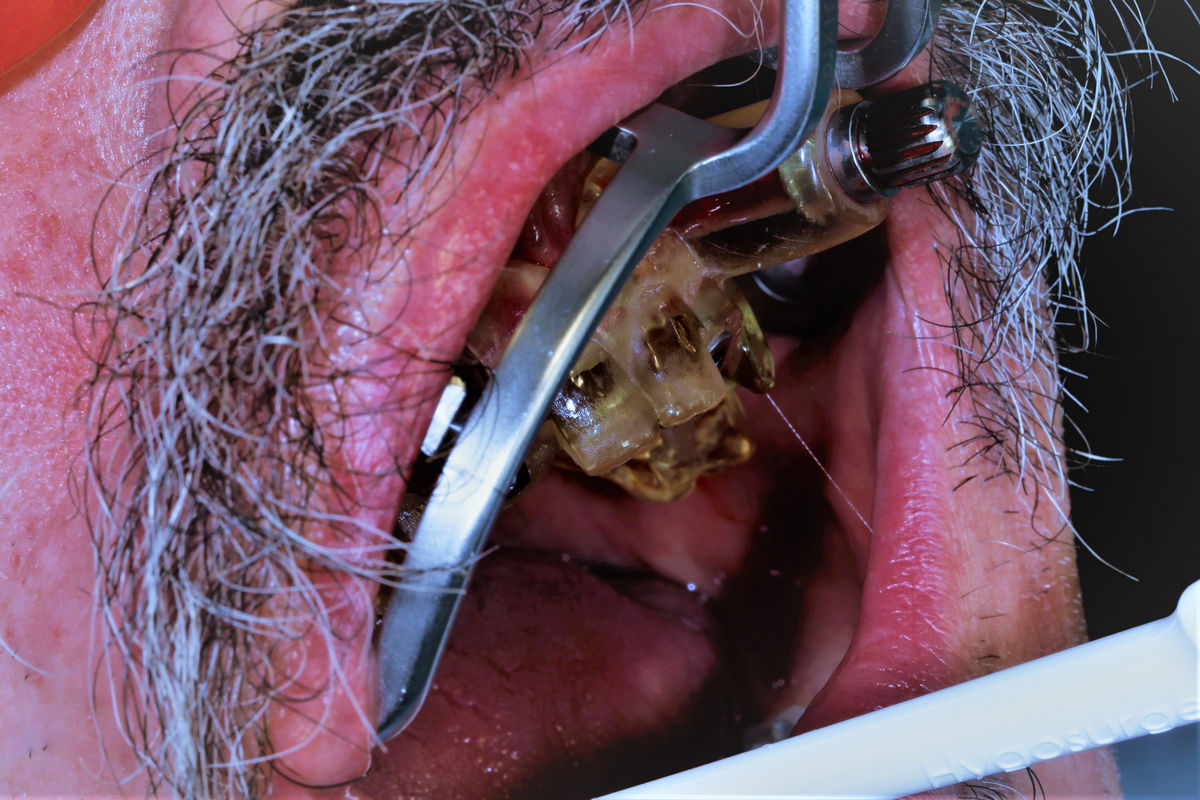

Chirurgia implantologiczna to temat wiodący 5 Sesji X Sezonu Practiculum Implantologii, która się odbyła 23-24 października 2020 roku. Bierze w nim udział 16 adeptów implantologii stomatologicznej. Zabiegi z udziałem Pacjentów jak zwykle poprzedziło omówienie i planowanie, tym bardziej, że zgodnie z planem wykonana została implantacja z wykorzystaniem szablonu chirurgicznego, który przygotowało laboratorium dentystyczne Wiligała Lab. Kursanci wykonywali szereg zabiegów implantologicznych i chirurgicznych oraz regeneracyjnych z zastosowaniem PRF, w tym sinus lift. Przeprowadzali je pod kierunkiem Lidera Umiejętności Implantologicznych dr n.med. Violetty Szycik, która wysoko oceniła wykonanie zabiegów.